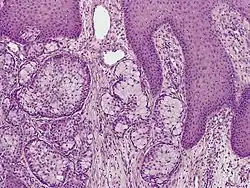

A skin biopsy is the most common test used to diagnose eccrine carcinoma.[2] The biopsy will detect growth of new or abnormal tissue. Another test that can be performed is using immunohistochemistry, but it is inconsistent.[2] Markers used to detect eccrine carcinoma consist of carcinoembryonic antigen, progesterone receptors, estrogen receptors, epithelial membrane antigen, pancytokeratins, and cytokeratin 7.[5][6]